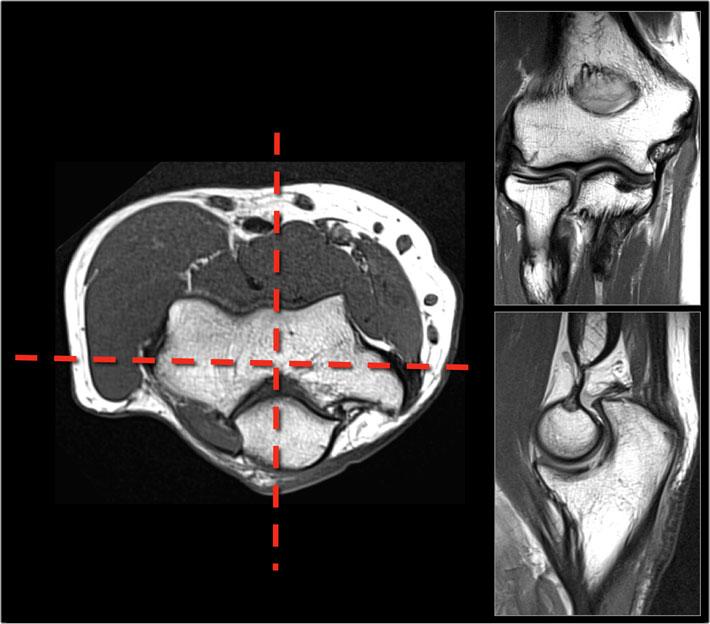

Giống như ở vai, bạn cần đảm bảo thu nhận các mặt phẳng hình ảnh một cách chính xác theo chuẩn hóa.

Sử dụng trục của các mỏm trên lồi cầu trên ảnh định vị axial để lập kế hoạch quét mặt phẳng coronal.

Các hình ảnh sagittal được quét vuông góc với lát cắt coronal.

Bằng cách này, bạn sẽ có được những hình ảnh rất bền vững và sẽ quen với giải phẫu bình thường.